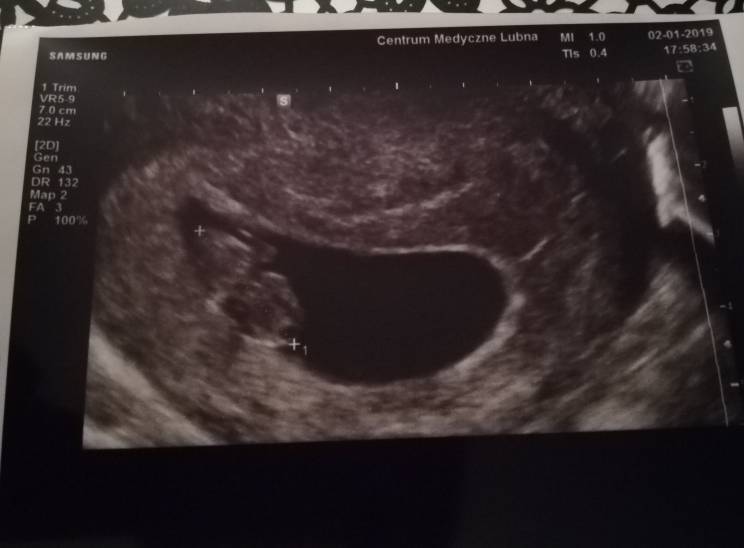

Przedstawiam Wam moją fasoleczkę. Moje całe 2,06cm szczęścia ma już nóżki i raczki, widziałam bijące serduszko. [emoji171]

Lenati super, że u Ciebie też wszystko w porządku. Trzymam kciuki za kolejne wizyty. Zobacz załącznik 929758